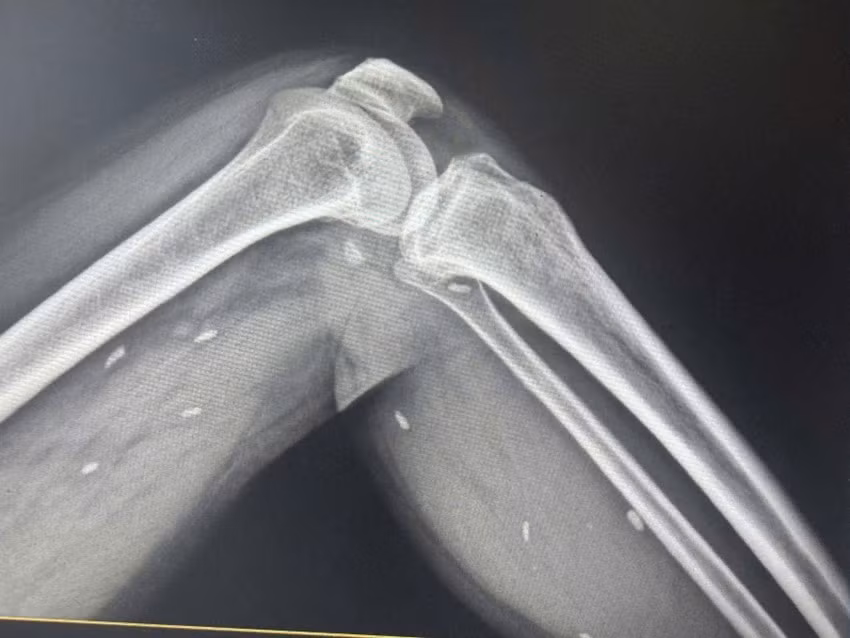

Người bệnh T.T.H đến Trung tâm y tế để thăm khám sau khi có dấu hiệu mệt mỏi, đau nhức nhiều ở vùng chân, lưng và vận động khó khăn. Bác sĩ đã chỉ định chụp X- quang để kiểm tra.

Nhiều kén sán nằm trong mô vùng xương đùi và cẳng chân bệnh nhân/Ảnh plo.vn

Kết quả cho thấy nhiều kén sán có kích thước tương đương hạt gạo, nằm rải rác trong các mô mềm vùng xương đùi và cẳng chân. Bác sĩ nhận định đây là hình ảnh điển hình của tình trạng nhiễm kén sán.